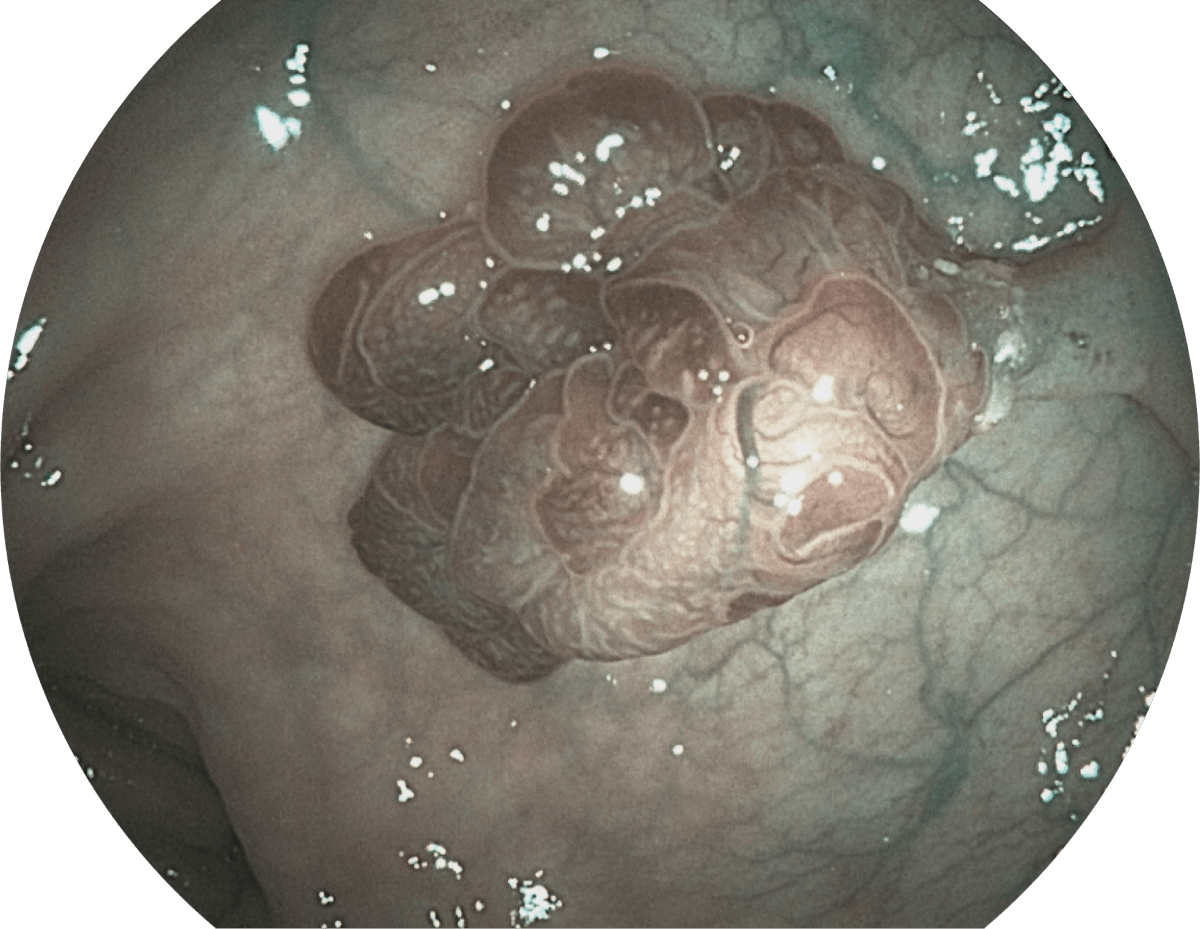

具有聚谱成像技术(SFI)及光电复合染色成像技术(VIST),可完美呈现粘膜细节及病变特征。

( Versatile Intelligent Staining Technology, VIST )